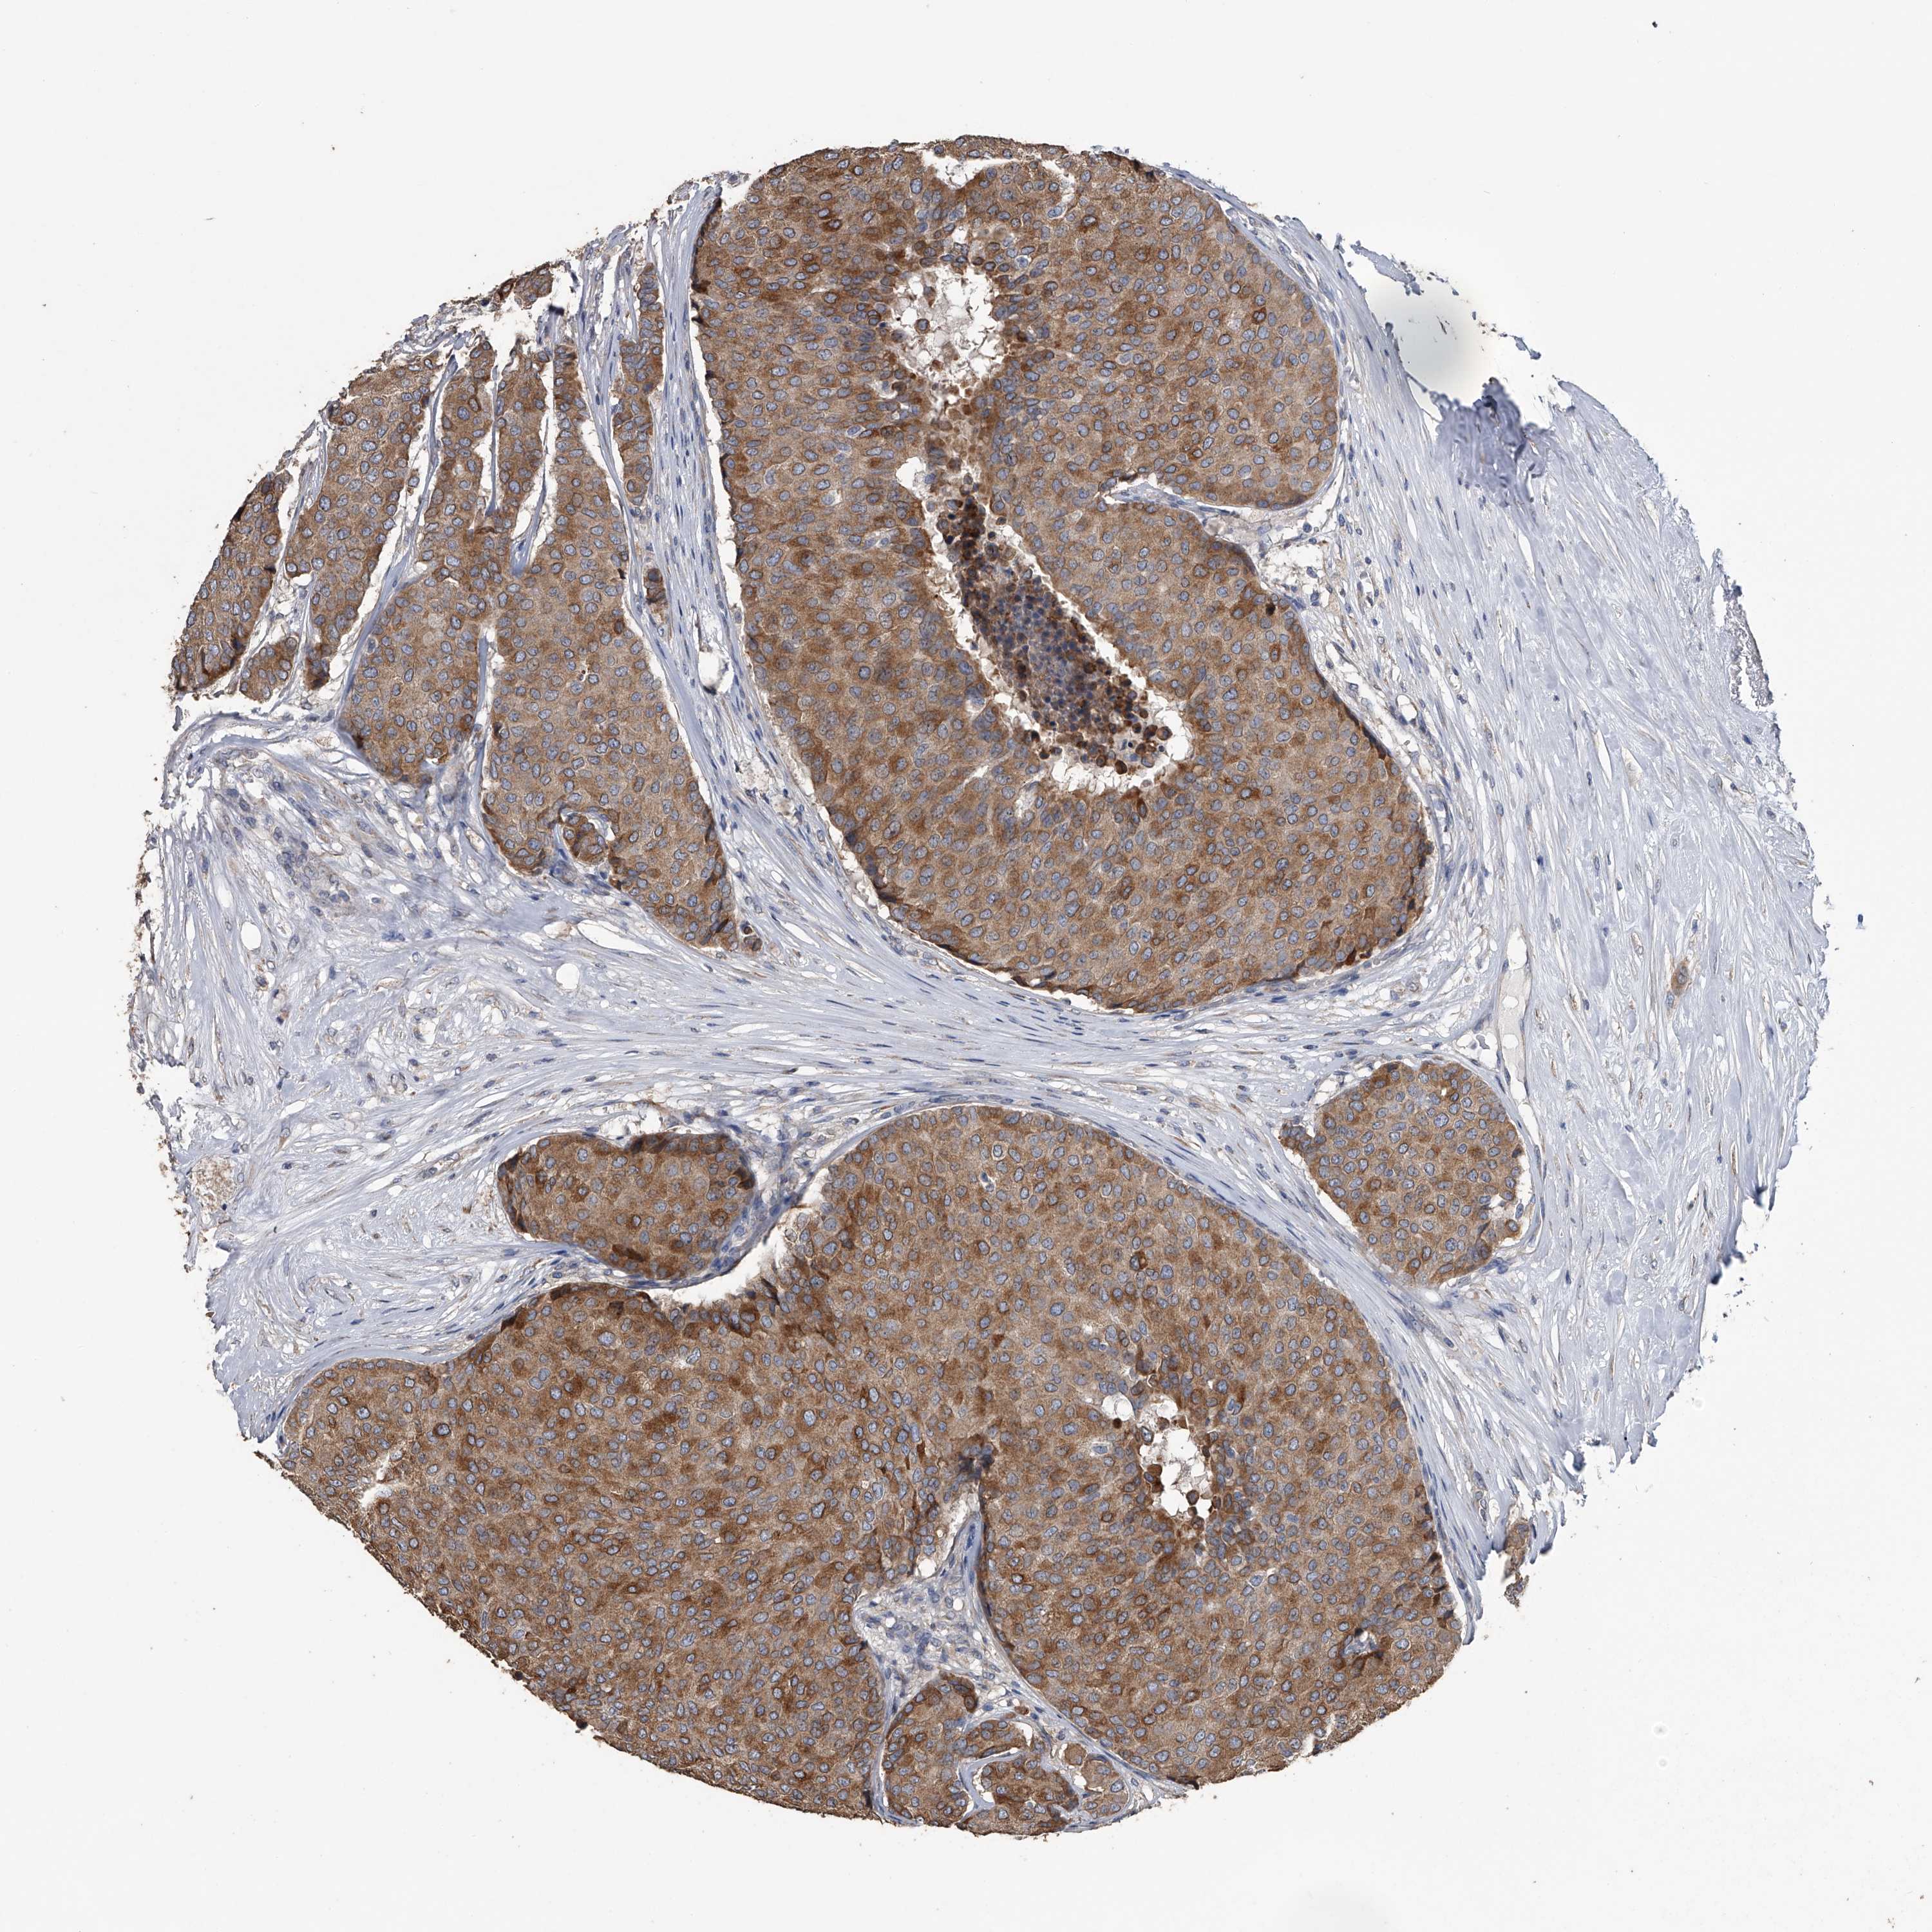

CANCER BREAST CANCER Show tissue menu

BRCA TCGA BRCA VALIDATION PROTEIN EXPRESSION